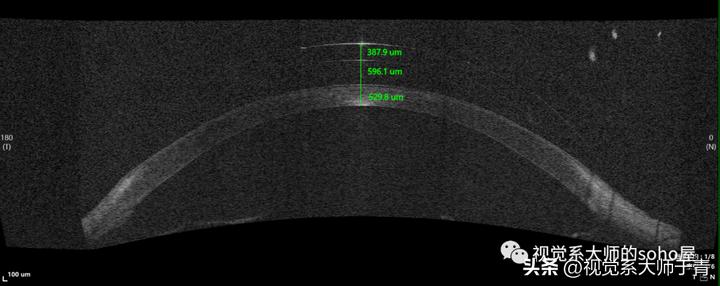

在实际验配时,常以佩戴者的角膜厚度做为评估基准,使用裂隙灯高倍率高光强平行六面体斜照法,估测镜下泪液层和角膜厚度的比例。如下图: